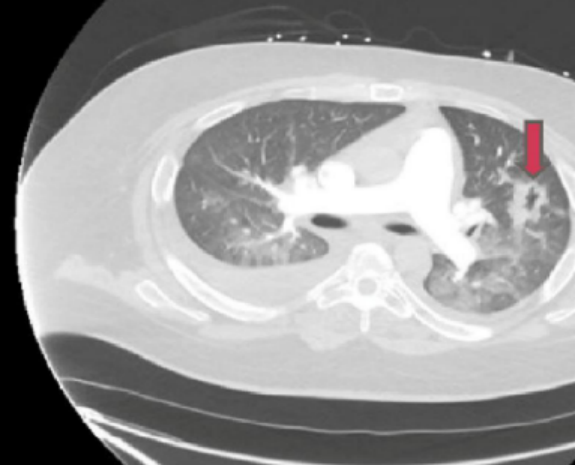

胸部CT增强扫描:肺血管充血、水肿,左上叶局灶性实变,左肺野空化病变,双侧胸腔积液,左上肺活检显示为非特异性炎症和纤维化。(图1)

图1 胸部CT增强扫描